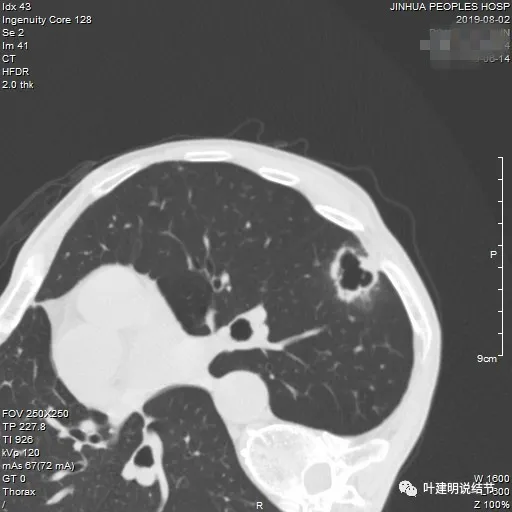

先看2024年6月的影像:

靠叶裂侧密度高、实性,灶内空腔多房,有微小血管走向并进入病灶的囊壁内,叶间裂有受牵拉。

囊壁明显厚薄不均,内壁也不光滑,而整体轮廓与边界却较为清楚。

部分边缘有细毛刺样征、中间密度低些,边上有囊腔,有的地方有少许磨玻璃成分,见到有小血管多处进入病灶。